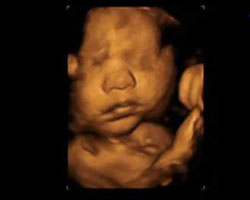

Em seguida, oferecemos-te um vídeo no qual poderás observar um feto de 38 semanas em movimento, bem como a evolução e o desenvolvimento do feto nesta semana próxima do parto, através da ecografia correspondente. Não percas!

Ecografia de 38 semanas